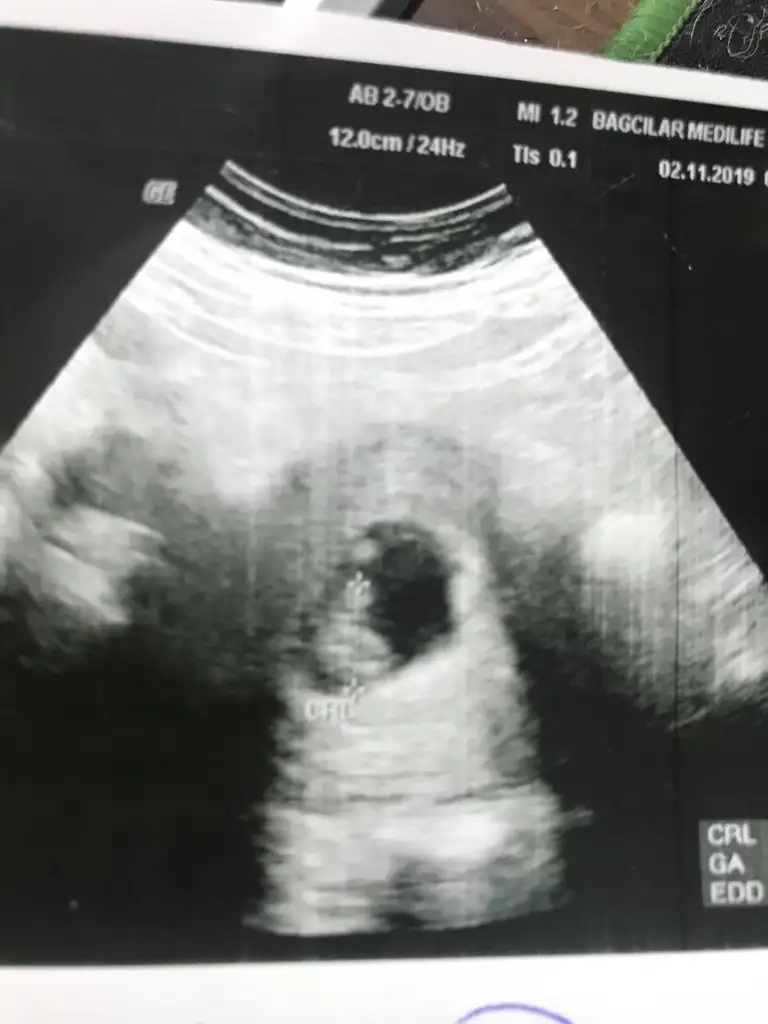

Usgniz 9 haftalık ve nub olmaz 11 yada 12 hafta olmalı o haftalarda tekrar paylaşırsınızAyy heyecanlandım:) nerden anladınız :)

Usg kaç haftalık ve usg karanlık çözemedim başka usg paylaşınIkra meyra kaç haftalığa kadar nub bakıyosunuz kız demiştiniz ama net değildi bide buna bakar mısınız

6 haftalık usg vajinalsa kız karından bakıldıysa erkek nub için 11 yada 12 hafta olmalıKızlar sizce benim bebişin cinsiyeti nedir biri 6 haftalıkken biride bugün yani 8 haftalık tahminleri alalıö bakalım teyzeleri

Yok hiç vajinal değil hepsi karından neyse iki hafta sonra tekrar atarım ozaman yinede sağolasınız ama karından erkek diyorsunuz öylemii6 haftalık usg vajinalsa kız karından bakıldıysa erkek nub için 11 yada 12 hafta olmalı

Evet karından erkek tabi 11 yada 12 hafta usg nub için paylaşırsınız nub dogrulugu dogru tabi usg netse pozisyon uygunsaYok hiç vajinal değil hepsi karından neyse iki hafta sonra tekrar atarım ozaman yinede sağolasınız ama karından erkek diyorsunuz öylemii